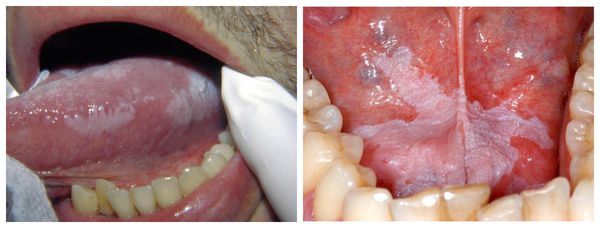

- и эритроплакия полости рта. При лейкоплакии наблюдается повышенное ороговение слизистой оболочки рта, при эритроплакии слизистая оболочка истончается [3] .

В полости рта:

- При лейкоплакии появляется налёт белого цвета, который сохраняется при чистке зубов, полоскании полости рта и после приёма пищи, при осмотре врач не может снять его шпателем. Термин «лейкоплакия» используется для тех образований, которые появляются в полости рта без очевидной причины.

- Эритроплакия — б олее редкое и опасное состояние. Для него характерно появление красного пятна на слизистой оболочке. Поверхность такого пятна бархатистая, иногда с изъязвлениями. Если во рту появился белый налёт, покраснение или припухлость вокруг каймы губ, которые не проходят больше двух недель, нужно сразу обратиться к врачу-стоматологу [3] .